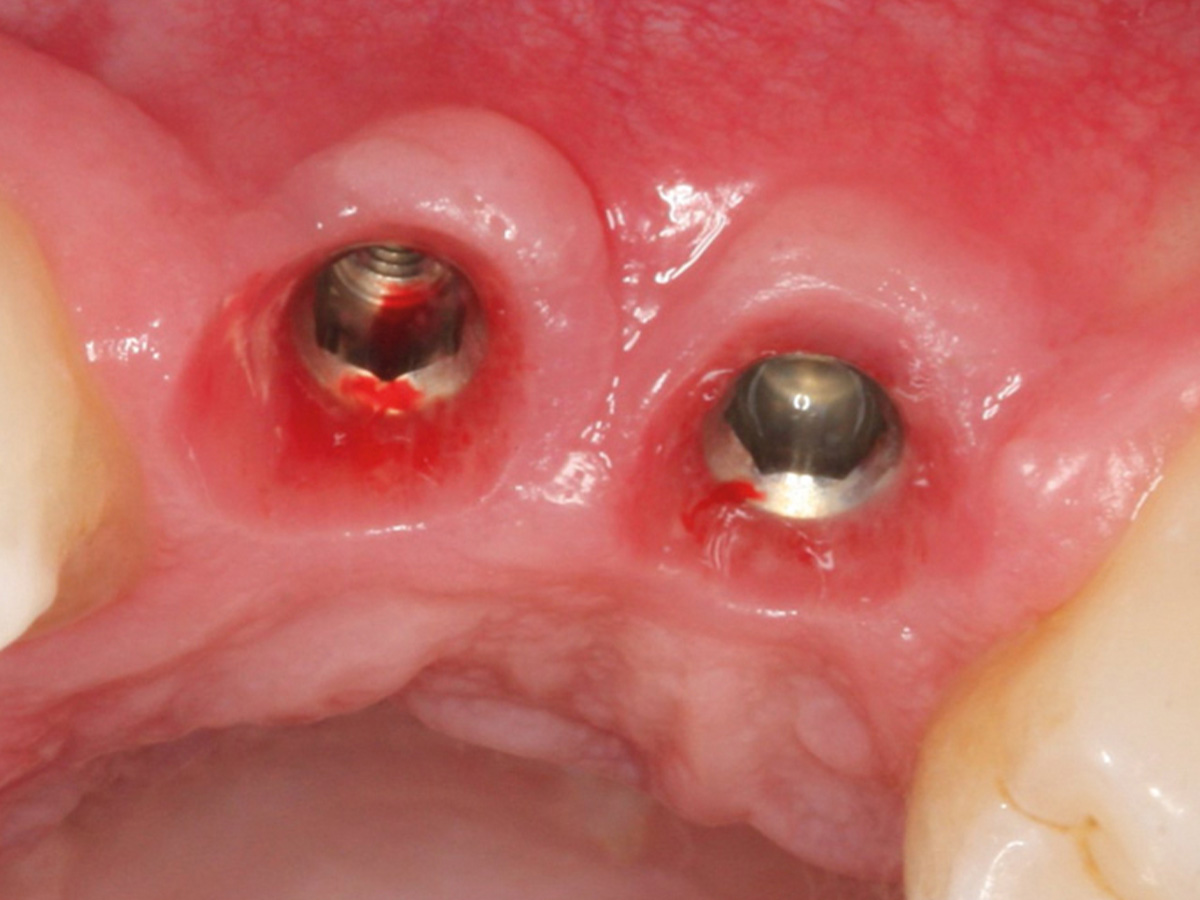

Abbildung 22

Darstellung der Implantat-Kavitäten im neuen Knochen.

Abbildung 23

Darstellung des Weichgewebes 2 Monate nach OP.